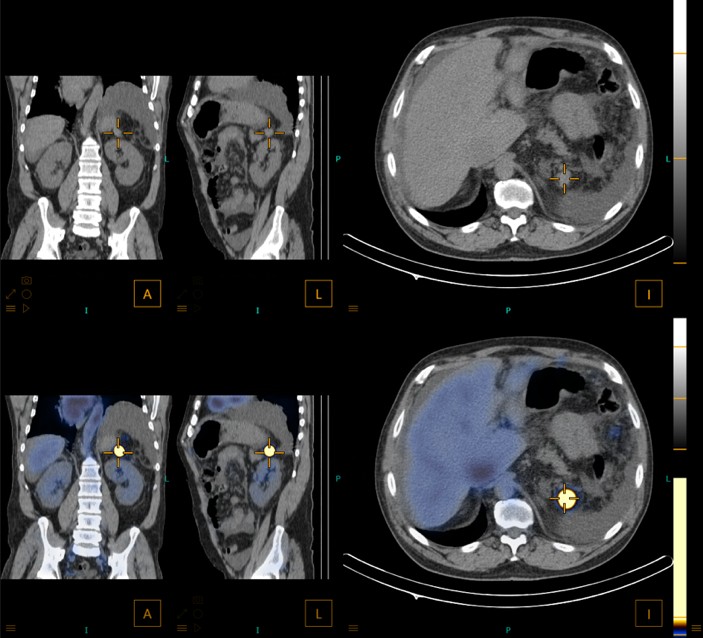

After multidisciplinary discussion and given the patient’s history of splenectomy, a diagnosis of splenosis was considered. A 99mTc-heat-denatured red blood cells (99mTc-DRBC) Single Photon Emission (SPECT)/CT (Fig.1) enhanced multiple and scattered foci with increased radiotracer uptake within the peritoneal cavity, that were coincident with the known unspecific abdominal nodules on CT (Fig.2) with variable size, confirming the splenosis hypothesis.

Figure 2: Nodule measuring 20x19mm posterior to the stomach on morphological images (non-contrast CT; top line) that is coincident with the foci with increased radiotracer uptake on 99mTc-DRBC SPECT/CT (bottom line).